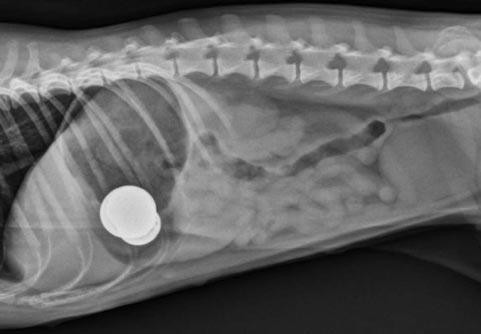

• Pemeriksaan x-ray